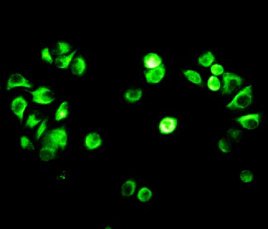

Способы применения первичных антител

Первичные антитела используют в разных методах: от вестерн-блоттинга до иммунофлюоресценции и проточной цитометрии. Всё решает подготовка: нужно грамотно выбрать буфер, точно рассчитать, сколько продукта добавить, и не затянуть с инкубацией. Например, в вестерн-блоттинге без правильной блокировки мембраны фон может всё испортить, а в иммунофлюоресценции фиксация клеток решает, будет ли сигнал ярким. Мы не просто продаём реагенты, а помогаем довести эксперимент до результата: подбираем реагенты и даём советы по методам, если есть специфика в протоколах производителя. Нужен особый подход? Оформите спецзаказ по ссылке — мы найдём решение для вашего проекта.